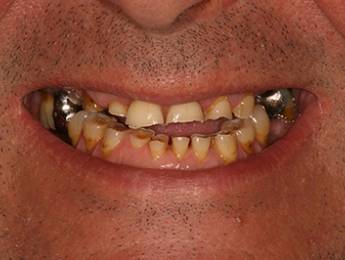

11. eset

27 éves páciensünk egész életében rettegett a fogorvosi beavatkozásoktól. Az összes foga elszuvasodott. A legkárosodottabb fogak gyökérkezelése és a szuvasodásainak megszűntetése után 26 fémkerámia koronát kapott a páciens. Erre a kezelésre is nagyon büszkék vagyunk. 2 hét leforgása alatt sikerült jelentős mértékben javítanunk a páciensünk mosolyán, önbizalmán és mióta velünk talalákozott, már a fogászati kezelésektől sem fél annyira!